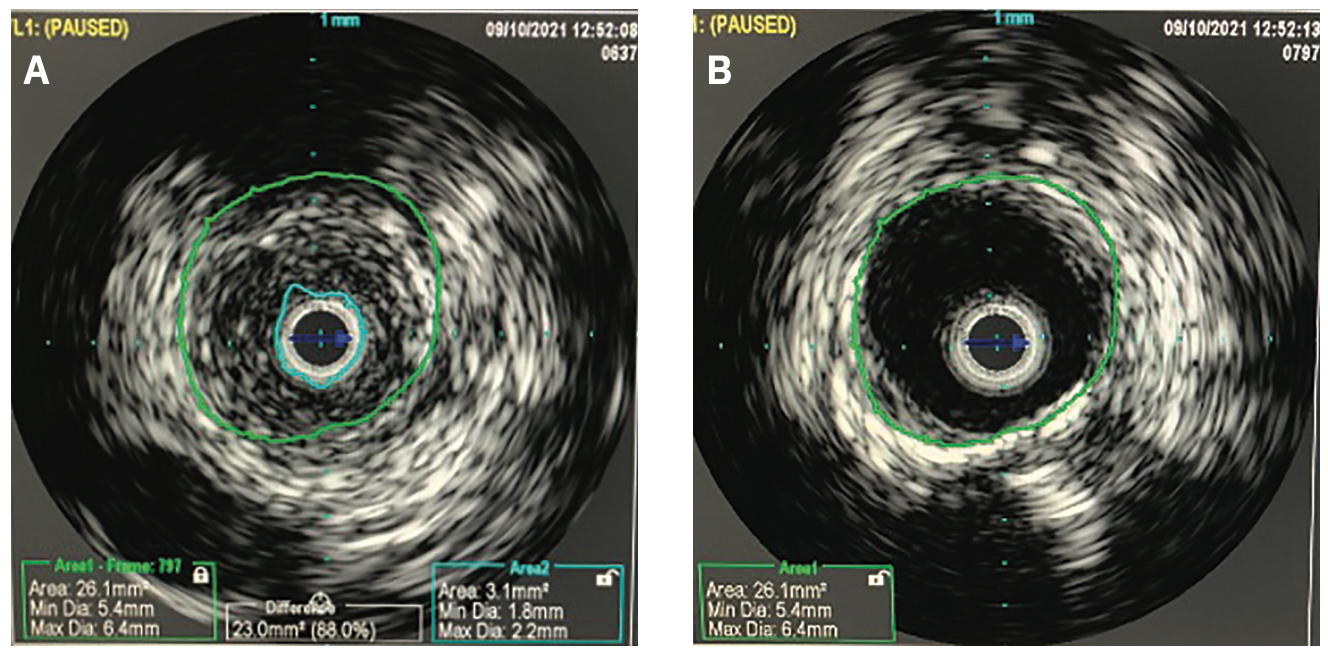

A formal right lower extremity arteriogram was subsequently performed and revealed a critical stenosis of the distal common femoral artery and proximal PFA (Figure 1). The SFA was occluded to its ostia and the proximal aspect of the stent was found to be fractured. There was reconstitution of the P3 portion of the popliteal artery and runoff to the foot via a patent but moderately diseased peroneal and posterior tibial artery. The femoral bifurcation lesion was further evaluated with intravascular ultrasound (IVUS), which revealed a concentric 88% stenosis composed of primarily soft plaque (Figure 2A).

To begin the case, diagnostic angiography was paired with IVUS of the right femoral bifurcation lesion to provide maximal information. Key details provided by the IVUS exam included that of soft plaque or intimal hyperplasia (with minimal to no calcium present), as well as the presence of concentric disease. Vessel diameters were assessed by IVUS to ensure that balloons were appropriately sized and thus would minimize the risk of dissection.